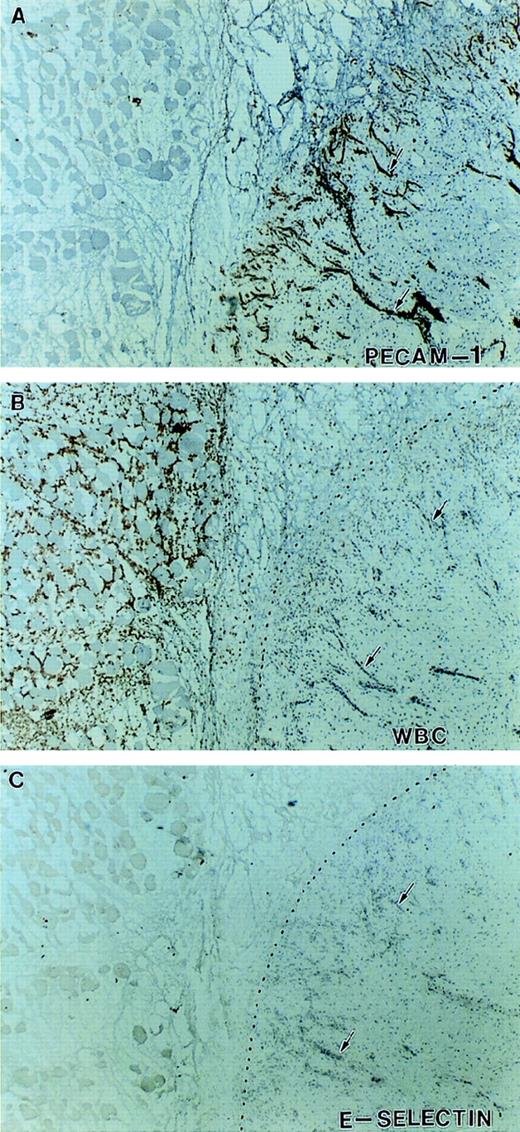

Expression of E-selectin in inflamed tissue. Immunohistochemical staining of serial sections at the junction between viable and necrotic tissue indicated by the dotted line. Sections were stained with antibodies against PECAM-1 (A), Mac-1 (B), and E-selectin (C). There is intense neovascularization at the interface of viable and necrotic tissue (A) and infiltration of Mac-1–positive leukocytes (neutrophils and monocytes) in the necrotic tissue (B). Despite this indication of active inflammation, no significant expression of E-selectin was detected on any of the vessels in this tissue (arrows).

After the patient’s amputation (see Patient history), tissue from the necrotic muscle flap, the nonhealing ulcer and the surgical margin were obtained and processed for immunohistochemical staining. The availability of this tissue provided the opportunity to evaluate the expression of cell adhesion molecules on the endothelium of her vasculature known to be involved in leukocyte recruitment. Immunohistochemical staining of multiple (>6) tissue sections from three distinct sites were performed. The margins of the ulcer showed that although PECAM-1, ICAM-1, and P-selectin were expressed on the vasculature, no expression of E-selectin was detectable on the vessels (large or small) from inflamed tissue (Figs 6 and7). Staining with 3 different anti–E-selectin antibodies gave similar results. There was also patchy staining for VCAM-1 on her endothelium (data not shown). Figure 8 shows serial sections of tissue from the junction between necrotic and viable tissue. In this obviously inflamed tissue, as evidenced by the presence of Mac-1 positive leukocytes (neutrophils and monocytes) and intense neovascularization, no expression of E-selectin was noted on the vasculature. In contrast, staining of tissue from the margins of chronically infected nonhealing wounds/ulcers located on the lower extremities of 2 diabetics who were at risk for amputation showed the expression of E-selectin on vessels in these tissues (Fig9). Of note, although our patient appeared clinically to manifest less pus formation, the presence of extravascular leukocytes as indicated in Fig 7, suggests that her leukocytes still had some capacity to migrate into sites of infection or injury.

Although our patient did not have evidence of a leukocyte adhesion deficiency, she did show a striking absence of E-selectin from the surface of the endothelium despite inflammatory stimuli (Figs 6 through8). These observations were supported by the finding that in skin organ cultures, TNF-α increased the vascular expression of E-selectin in normal, but not patient, skin (Fig 10). E-selectin message was found in inflamed tissues (Fig 11), and although E-selectin was not present on the endothelium, its message was translated as evidenced by the high levels of circulating sE-selectin (Table 2). As significant mutations in the E-selectin gene were not detected, the absence of endothelial E-selectin does not appear to be the result of a secreted alternatively spliced or mutational variant. This is supported by the finding that the molecular species of sE-selectin detected in the patient and control sera were of the same molecular weight (Fig 12). Of note, her serum did not inhibit the TNF-induced expression of E-selectin on HUVEC (data not shown), suggesting that proteolytic activity in her serum was not responsible for the loss of surface endothelial E-selectin. We therefore propose that there may be upregulation of proteolytic activity on the surface of the vascular endothelium of the tissues we studied that results in markedly accelerated release of E-selectin from the endothelial surface. As the entire vasculature was not surveyed, our data do not exclude the possibility that in specific organs, such as the lung and the gastrointestinal tract, the vasculature may be normal.

An important question is how might the loss of the endothelial surface expression of E-selectin with an accompanying increase in circulating sE-selectin increase the susceptibility to infection in this patient? There are a number of possibilities. First, given the role of selectins in the initial rolling phenomena, the loss of endothelial surface expression of E-selectin may compromise the ability of leukocytes to roll along the endothelium and therefore impair leukocyte emigration into sites of inflammation. However, mutant mice deficient in E-selectin do not show an increased incidence of spontaneous infections, and neutrophil recruitment in response chemical-induced peritonitis is impaired only if P-selectin is also simultaneously blocked.26 These and other studies with selectin-deficient mice27 28 suggest that with respect to the process of leukocyte recruitment, E- and P-selectin may serve redundant functions, and/or that in the setting of chronic loss each may be able to compensate for the persistent absence of the other. Consistent with this proposal is the demonstration in our patient of P-selectin endothelial expression and some extravascular accumulation of Mac-1–positive leukocytes in chronically inflamed tissues (Fig 8). While data from mutant mice are very instructive, its is possible (and probably likely) that the specific or relative functions of P- and E-selectin in humans differ from that of mice, and therefore care should be exercised in extrapolating from the murine studies.